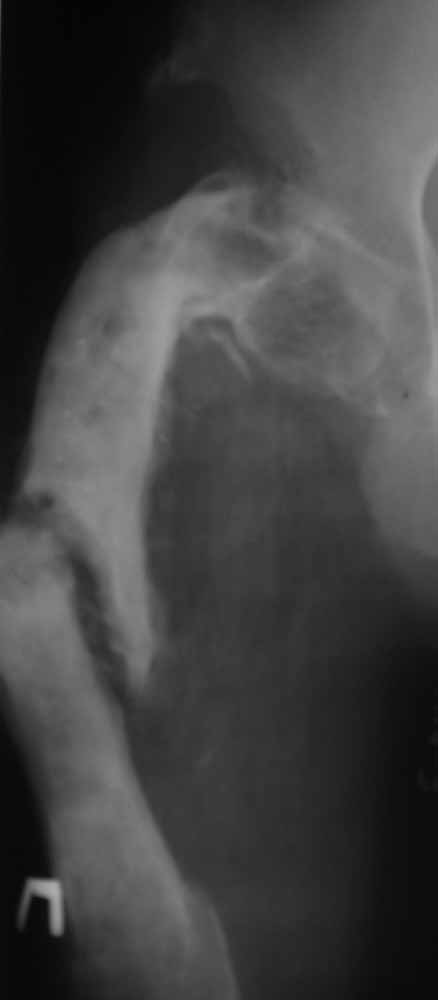

Infected Non-union, Coxa vara

Пациент 29 лет. Неоднократно оперированная Coxa Vara.

В анамнезе этапные операции по поводу устранения Coxa Vara, формирование артродеза коленного сустава, удлинения бедра. В данный момент беспокоит укорочение 7 см, эквинус стопы. Объективно: - местный статус виден на фото, сосудистых и неврологических расстройств нет. Обратился в консультативном порядке, настроен на удлинение голени в г.Волгограде. (со слов больного - не берут без санации очага на голени). Ваши предложения? Из кулуарных соображений - а не актиномикоз ли это? Иссечение рубцов+ VAC+ Стержень с аппаратом + микрососудистый трансплантат(?)

Ваш вопрос, коллега, вполне правомерен. В советское время те из нас, кто занимался костно-гнойной инфекцией видели достаточное количество подобных несчастных, кочующих из стационара в стационар. Своеобразный госпитализм приводил к тому, что люди тратили всю свою, как правило достаточно короткую жизнь, на лечение зачастую реально неизлечимых процессов. В данном случае имеющаяся рентгенологическая картина груботрабекулярной перестройки кости, сочетающаяся с участками склероза говорит, скорее всего, о том, что вся имеющаяся картина, дополненная чудесными фотографиями,вполне укладывается в клинику гематогенного остеомиелита, которым и страдает пациент с детства. Никакие санации, к сожалению, не приведут в данном случае к излечению, так как все имеющиеся рубцы являются зоной жизни этой самой инфекции. При продолжении лечения не исключено достаточно раннее развитие амилоидоза в этом случае. Мне кажется, что оптимальным было бы определить пациента в институт протезирования и протезостроения или в то учреждение, которое в регионе выполняет данную функцию. Специалисты помогли бы определиться с уровнем ампутации, являющейся, по сути, единственным способом разорвть порочный круг и дать пациенту возможность какой-то социальной адаптации. А в плановом порядке, насколько мне известно, можно добиться неплохого финансового обеспечения под протез конечности по квоте. Другого решения здесь нет. С уважением, Андрей Волна

извините за очепятку - не берут без санации очага на бедре. Сейчас имеется отделяемое из нижнего свища с периодическим выходом секвестром в виде мелкой крошки. Движений в ТБС почти нет - есть только сгибание градусов до 10. В стопе - только качательные.